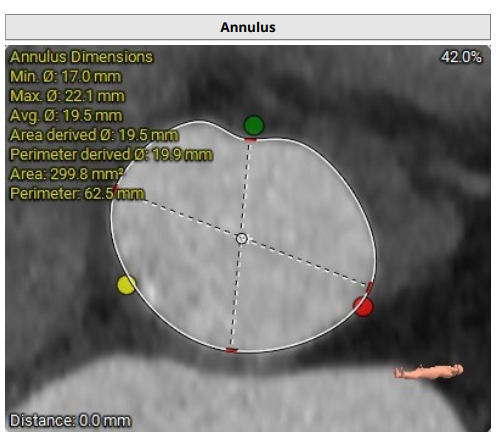

主动脉瓣呈三叶瓣,收缩期瓣环:299.8mm²;收缩期流出道:290.9mm²;

法式窦空间小;STJ高度17.4mm,均径26.4mm;升主动脉40mm处均径36.1mm;心脏角度52°;

LCA:10.4mm;RCA:13.2mm;窦部空间小,右冠风险不排除;

瓣叶增厚,轻度钙化,分布在瓣缘和窦底;

对合缘对齐(Commisure Alignment)角度为 83°;室间隔膜部长3.6mm;

使用20mm瓣膜进行术前模拟并评估冠脉遮挡风险;